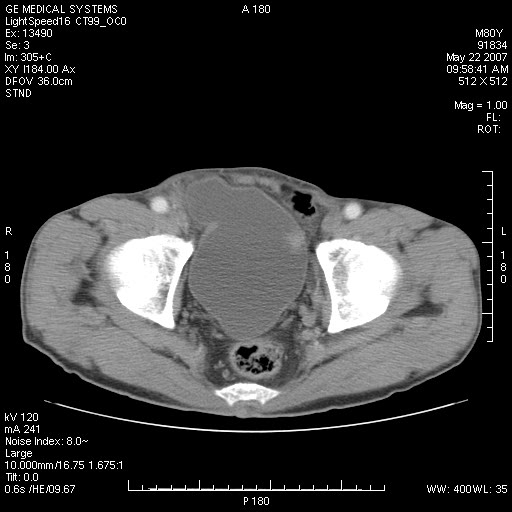

标题: CT8346:男,80岁。血尿,肝脏,膀胱占位,是否为肝转移?

男,80岁。血尿,无腹部不适病史。

膀胱病变:

肝脏内病灶有假包膜,增强扫描动脉期有动静脉瘘,有快进快出特点,考虑原发性肝癌。病灶内有裂隙样低密度影,以纤维板层样细胞癌可能性大。膀胱左侧乳头状占位,增强呈明显强化,左侧盆腔内有肿大淋巴结,结合有血尿病史,考虑膀胱癌左侧盆腔淋巴结转移。